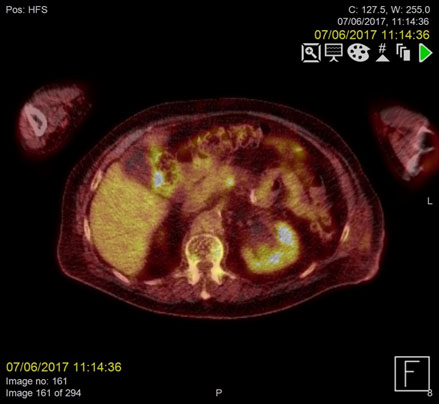

F18-FDG PET images were acquired from the skull base to the mid-thighs together with low dose CT for attenuation correction and anatomical co-location. This showed no malignancy but demonstrated high activity at the sites of the thrombus within the confluence of the SMV and portal vein as well as the distal IMV, in keeping with infected thrombi.

Repeat F18-FDG PET- CT images acquired two months later demonstrated complete resolution of the IMV and SMV thrombi (Figure 1-2).

Figure 2a. Metabolically active, infected thrombus at the confluence of the superior mesenteric vein (SMV) and portal vein demonstrating increased FDG uptake on PET/CT pre-treatment